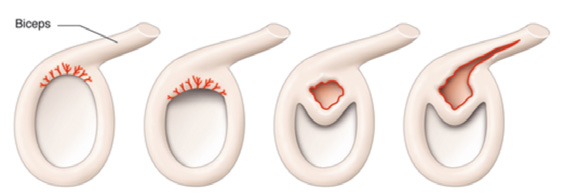

La lesión SLAP es la afección de la inserción o anclaje del tendón de la porción larga del bíceps en el hueso glenoides que forma parte de la articulación del hombro. Esto genera mucho dolor y limitación para movimientos del hombro. puede percibirse un resalto o chasquido en algunos casos.

Los desgarros pueden ser parciales o pueden ser completos, presentando dificultad o incapacidad para elevar el brazo.

Causas: edad (más frecuente en mayores de 40 años), traumatismo o esfuerzo mayor, actividades deportivas, lanzamiento de pelotas, levantamiento de pesas, sobre los hombros o cabeza, degeneración del tendón.